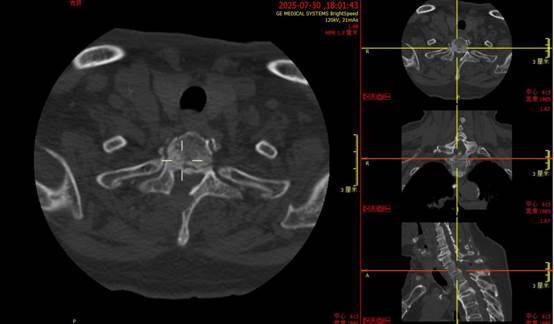

▲图为术后椎管内受压解除情况